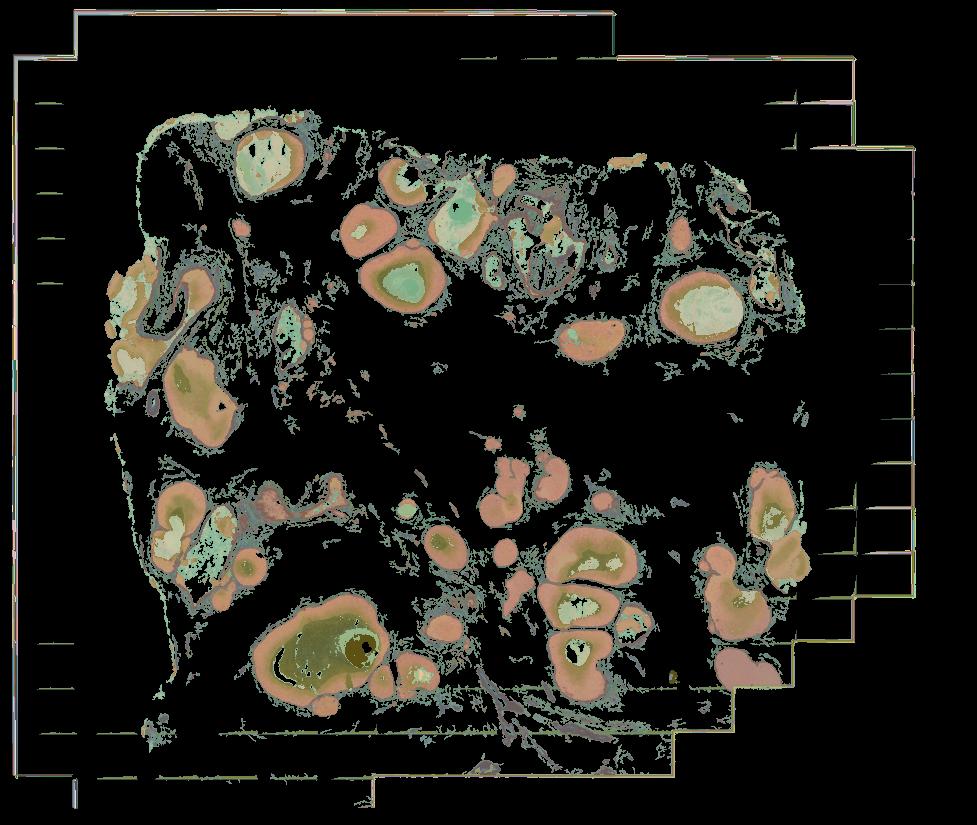

To study the spatial interactions among cancer and non-cancer cells1, we here examined a cohort of 131 tumour sections from 78 cases across 6 cancer types by Visium spatial transcriptomics (ST). This was combined with 48 matched single-nucleus RNA sequencing samples and 22 matched co-detection by indexing (CODEX) samples. To describe tumour structures and habitats, we defined ‘tumour microregions’ as spatially distinct cancer cell clusters separated by stromal components. They varied in size and density among cancer types, with the largest microregions observed in metastatic samples. We further grouped microregions with shared genetic alterations into ‘spatial subclones’. Thirty five tumour sections exhibited subclonal structures. Spatial subclones with distinct copy number variations and mutations displayed differential oncogenic activities. We identified increased metabolic activity at the centre and increased antigen presentation along the leading edges of microregions. We also observed variable T cell infiltrations within microregions and macrophages predominantly residing at tumour boundaries. We reconstructed 3D tumour structures by co-registering 48 serial ST sections from 16 samples, which provided insights into the spatial organization and heterogeneity of tumours. Additionally, using an unsupervised deep-learning algorithm and integrating ST and CODEX data, we identified both immune hot and cold neighbourhoods and enhanced immune exhaustion markers surrounding the 3D subclones. These findings contribute to the understanding of spatial tumour evolution through interactions with the local microenvironment in 2D and 3D space, providing valuable insights into tumour biology.